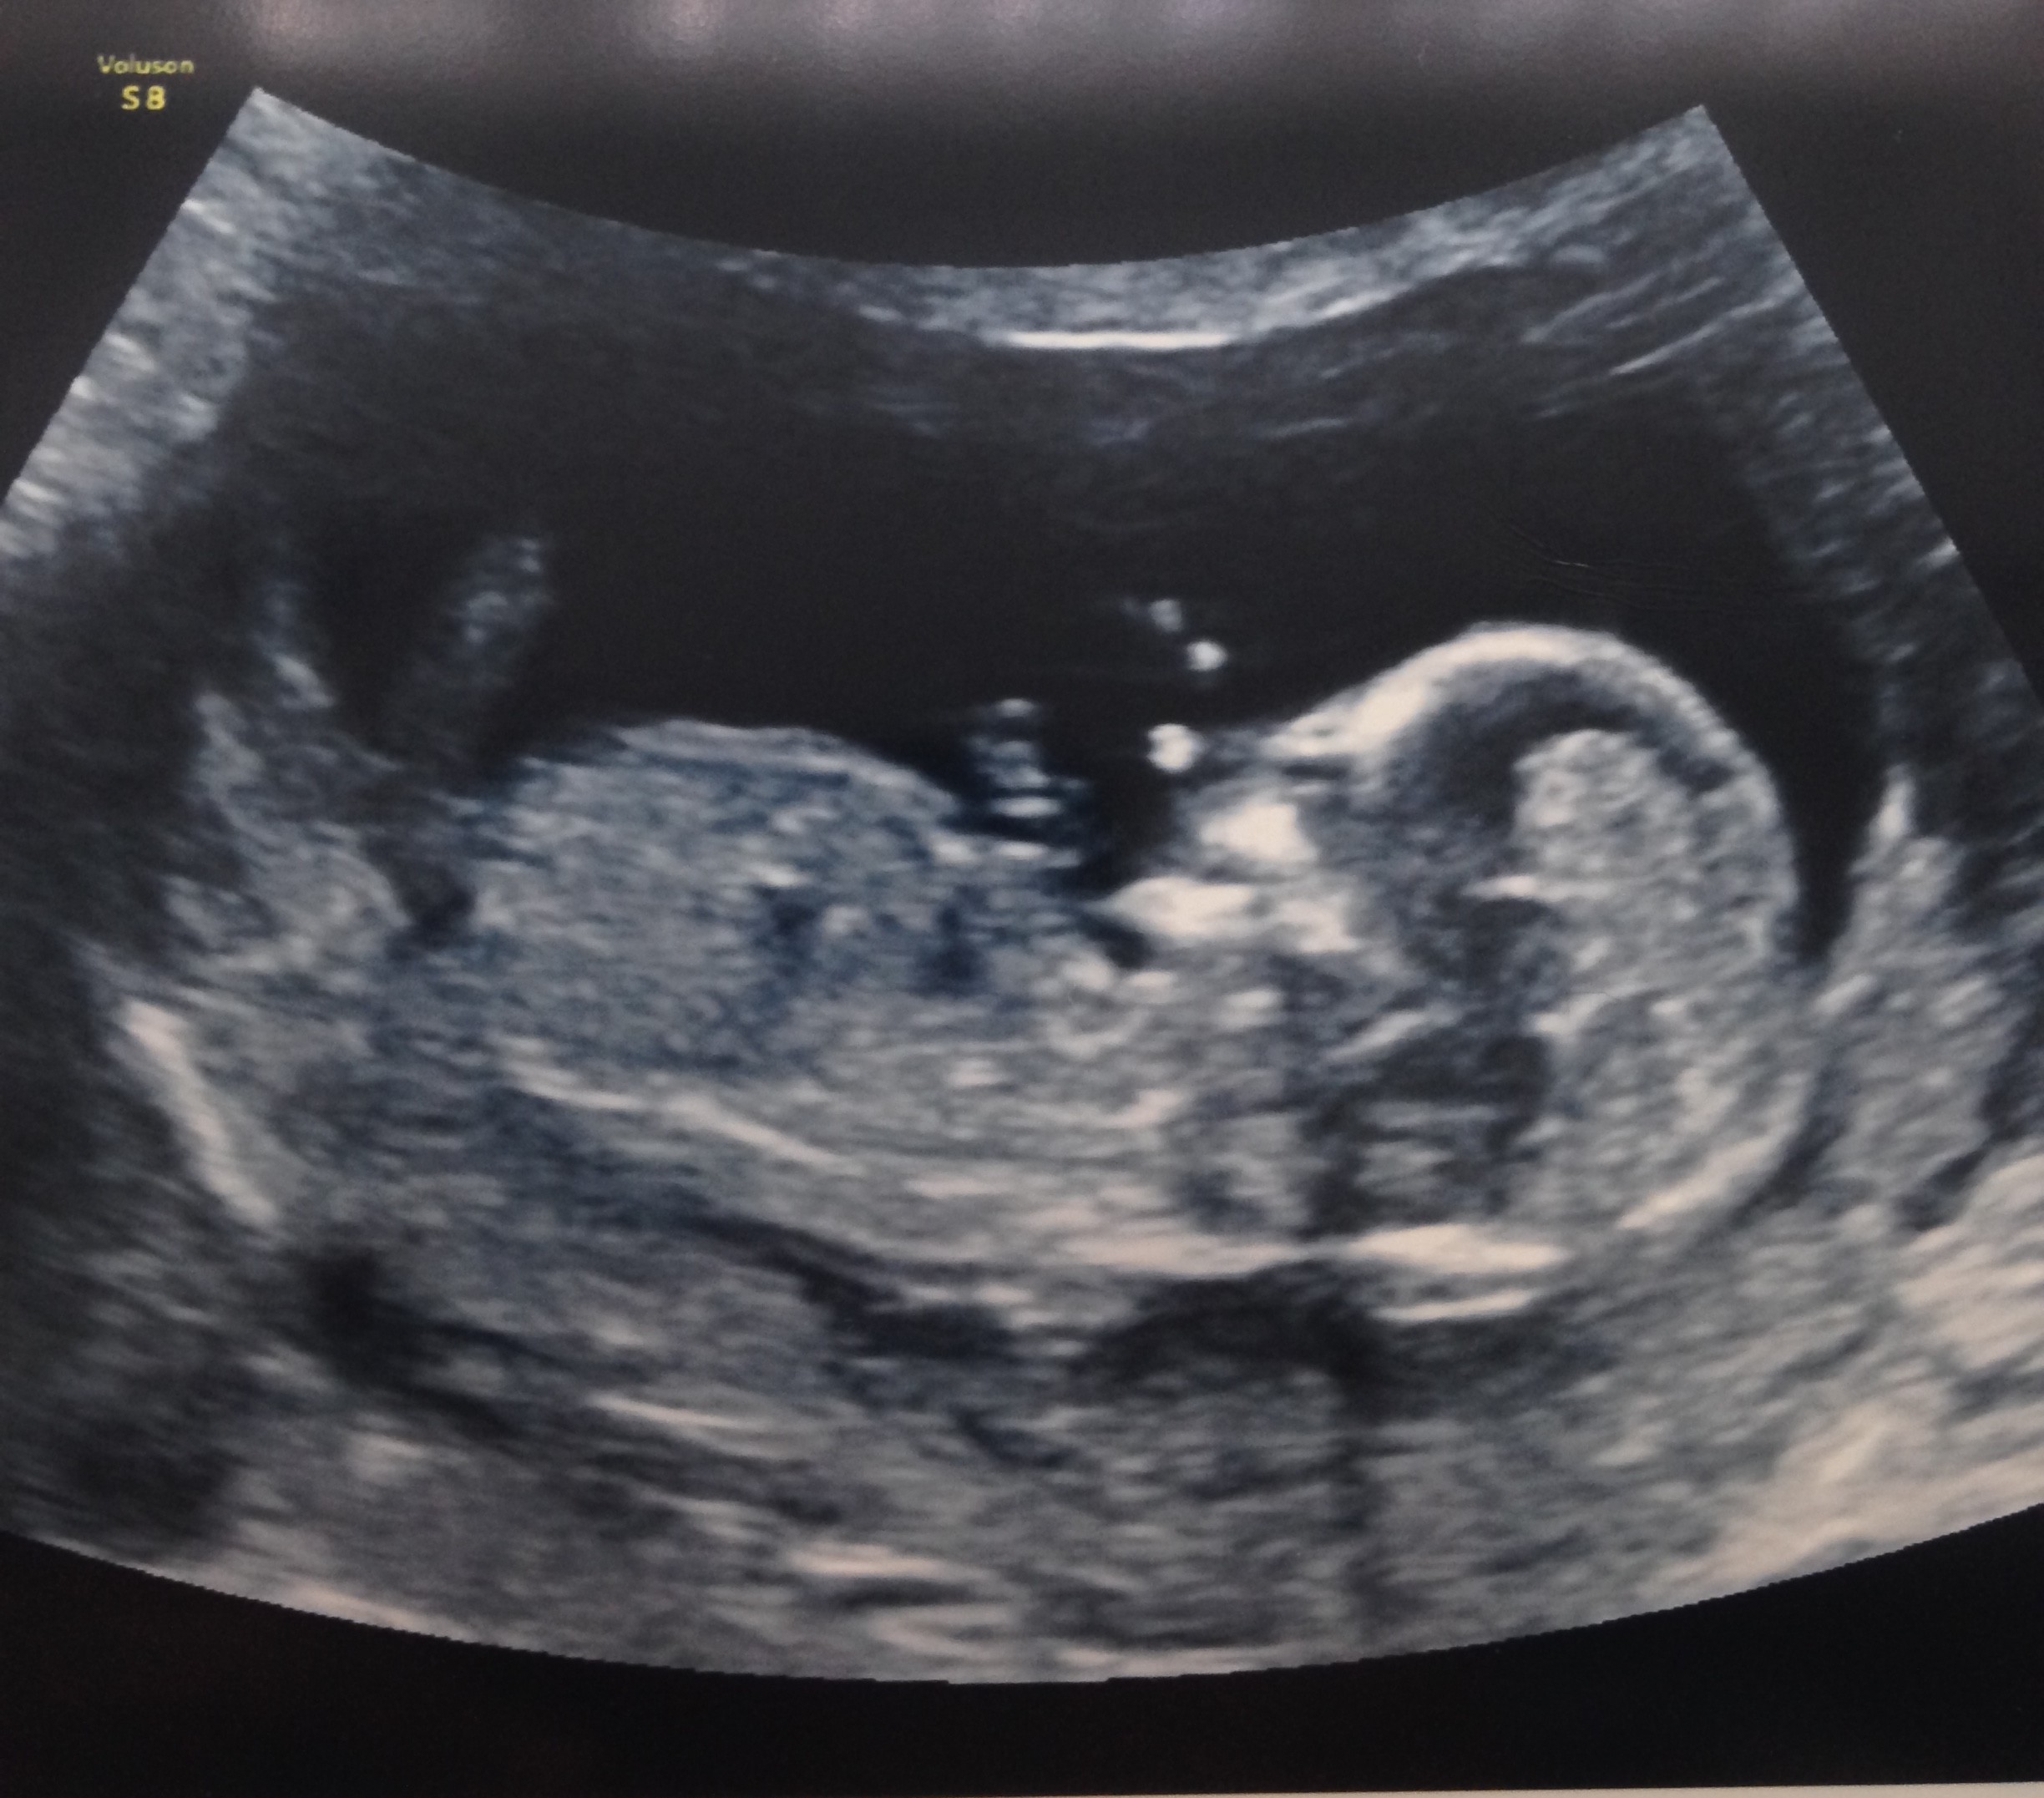

Merhabalar 11+5 günlük tahmininiz nedir acaba?

Ekli dosyalar

• IMG_6189.JPG

IMG_6189.JPG

552,4 KB · Görüntüleme: 548

• IMG_6190.JPG

IMG_6190.JPG

885,3 KB · Görüntüleme: 538

• IMG_6191.JPG

IMG_6191.JPG

918 KB · Görüntüleme: 512

Merhaba, yüklediğiniz görsellerde nub çıkıntısı görünmüyor. Bu yüzden değerlendirme yapamıyoruz. Sağlıklı gebelik geçirmeniz dileği ile..